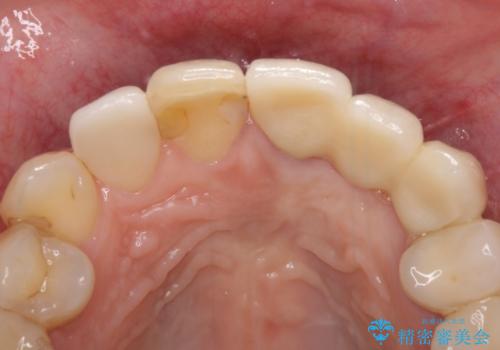

歯肉移植を用いた前歯のオールセラミックブリッジ

- 前歯が折れてしまい、ブリッジによる補綴治療を希望して来院された患者様です。

折れている前歯は抜歯をし、痩せてしまう歯肉は移植術により増大させることで審美面を回復した後、オールセラミックブリッジにて補綴することとしました。

インプラントかブリッジか悩むところでしたが、既に治療されている前歯のクラウン周りの変色が気になっていたため、ブリッジにより色調を合わせたオールセラミックを装着することを選択しました。

歯肉ラインや歯の形態、色調を整えることができ、患者様には大変満足していただきました。